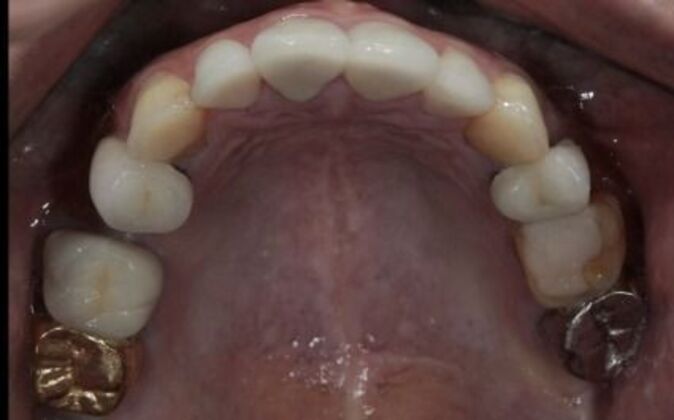

Full Mouth Reconstruction: Risa

Description

Full mouth reconstruction. When you see a client at a young age with so much dental work to begin with you consider your options carefully. You need to be aggressive in approach and conservative in maintaining as much of the healthy tooth structure. Have to consider the age of a patient whenever you embark on a major dental work especially when it involves redoing everything, repositioning and re-establishing a brand new bite position and correcting the inflammatory gum response from previous dental work. You cannot approach a case like this with a limited treatment plan that only addresses a few teeth. If this case is treated one tooth at a time you may leave the patient a “dental cripple”. By that I mean that this patient will constantly be at dental offices for the rest of her life addressing one broken down tooth after another until a cascading domino effect will render all the teeth in a hopeless condition. Here is a situation where we are dealing with multiple problems 1-bite collapse and malfunction 2-gum disease exacerbated by poorly fitting crowns 3-decaying teeth affecting the health of the roots This case had to consider all of these issues. Must understand that this patient is very young and has many years ahead of her so the dentistry has to be done meticulously, conservatively,aggressively and expeditiously. It’s a tough balancing act but as dentists we need to be realistic about our treatment objectives and have a proper plan that addresses dental breakdown. We were able to achieve the esthetic and functional concerns of the patient. Although we felt the color of the teeth were too bright. We do need to consider patients desires since they need to live with this for the rest of their lives and ultimately they need to be happy